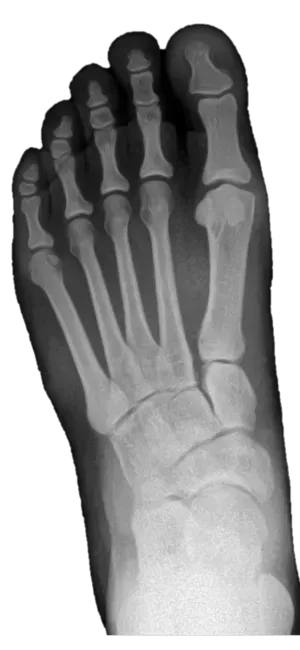

Digital X-Ray - Kansas City Foot and Ankle houses state-of-the-art digital x-ray technology that allows our physicians to review real-time x-ray imaging to share with patients during their appointment.